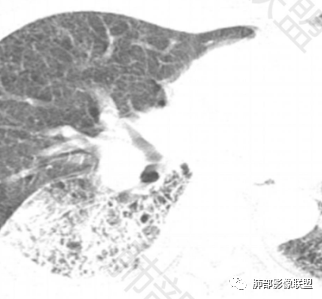

2.影像表现:肺气肿背景,右肺下叶呈现明显网格影及蜂窝影、枯枝征,边缘膨隆、叶间裂向前方推移。病灶密度不均,前份见不规则片状实性密度区,实性部分轻度强化,边界不清,周边特征掩盖不清。支气管主要分支显示,呈枯枝征。纵隔窗病灶密度偏低,病灶内血管影边缘稍显模糊,未见明显液化坏死区。

余双肺未见明显结节影。

右侧肺门淋巴结肿大,中央低密度;纵隔见轻度增大淋巴结。

3.综合分析:临床方面:慢性病程、急性发作,呼吸道症状伴发热,炎性指标升高,提示存在感染可能;CA199升高,但相对特异性不高。影像双肺气肿,右肺下叶蜂窝状改变明显,夹杂实变密度区,支气管相关但未见阻塞,较常见于感染性病变,如G-杆菌感染等。蜂窝影什么时候出现我们不得而知,实变区周边特征掩盖不清。

前后三月余病灶变化不明显,右肺门异常肿大淋巴结让人警惕恶性病变可能性。

因为有肺气肿背景、有蜂窝,周边特征及张力等都不能作为判断依据或参考。单肺叶蜂窝影伴实性密度区被确诊为肺腺癌的例子已不少见,敬请留意。